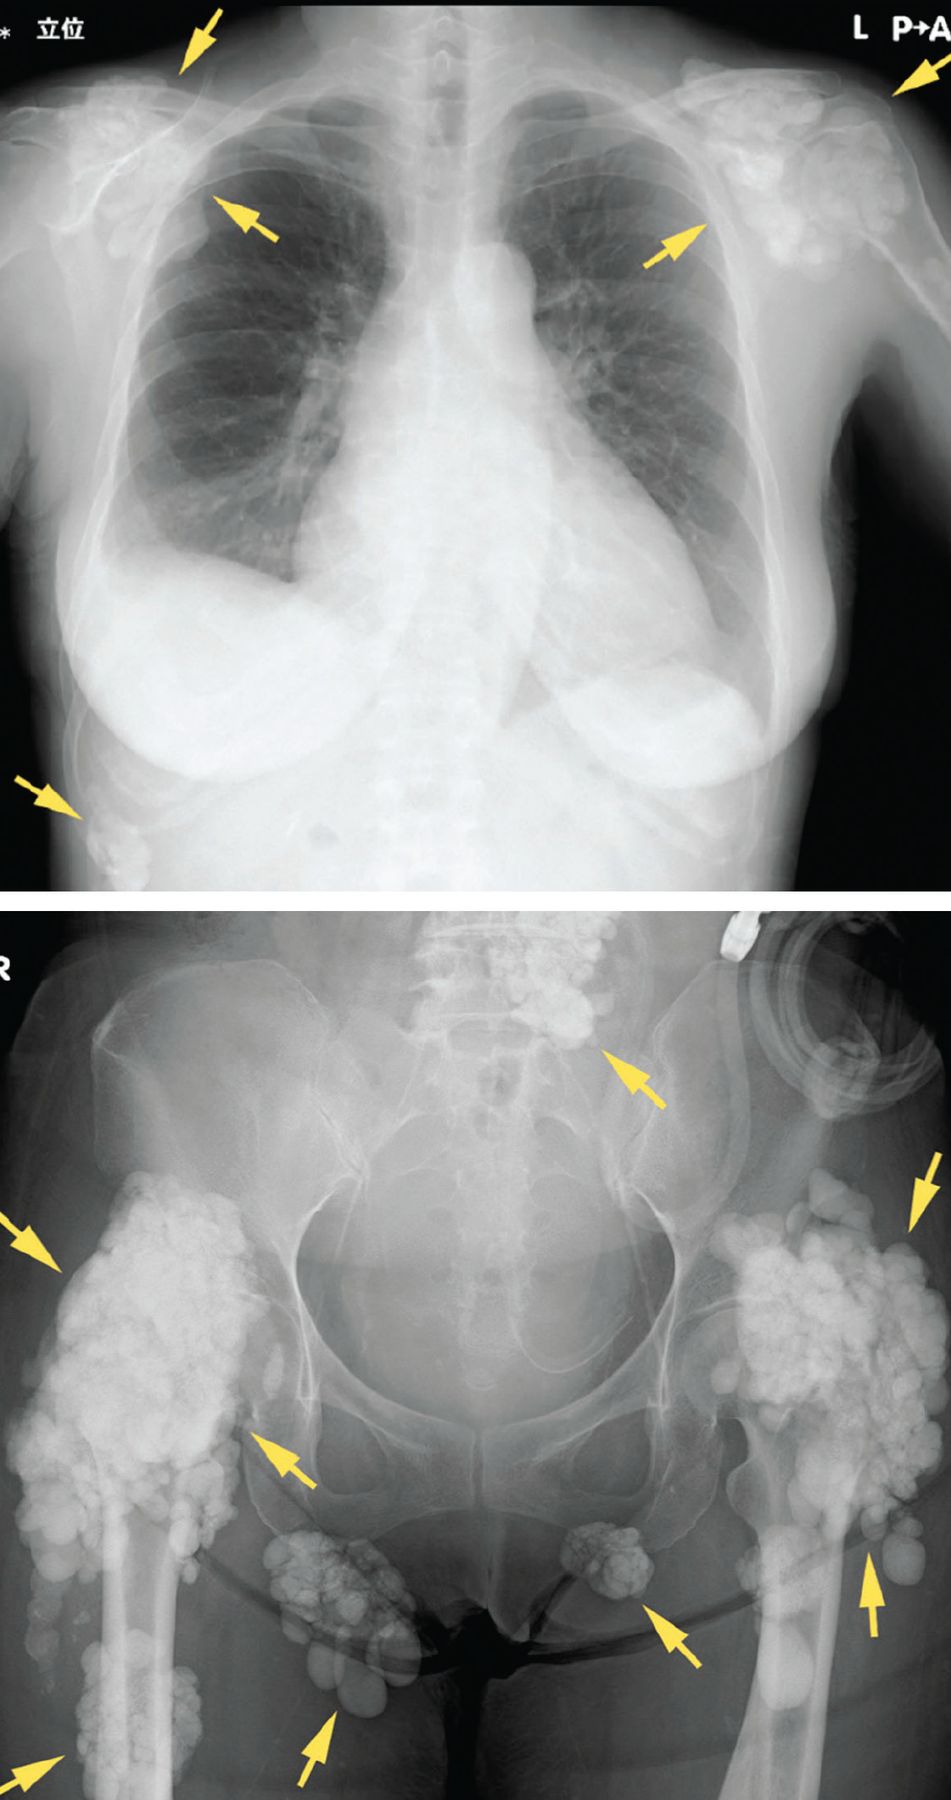

Calcification is just a sign of coronary atery disease and it can be prevented by lowering risk factors such as smoking, high blood pressure, diabetes, high. You may be able to prevent calcium deposits by monitoring your health and seeing your healthcare provider regularly. If cancer is found, treatment may include.

“pericardial tissue tends to bind calcium ions, which in turn bind phosphate ions, thus encouraging calcification of the prosthetic heart valve. Calcification and stenosis generally affect older adults. The regulated inclusion of this.

Aortic valve calcification may be an early sign of heart disease, even if there aren't any other heart disease symptoms. Water filters like ion exchange or reverse osmosis can remove up to 98% of the impurities in hard water, so technically, they can get rid of the calcium, but not all of it. A great and easy way to prevent calcium buildup is by applying a calcium prohibitor or blockerto the pool tiles or glass.